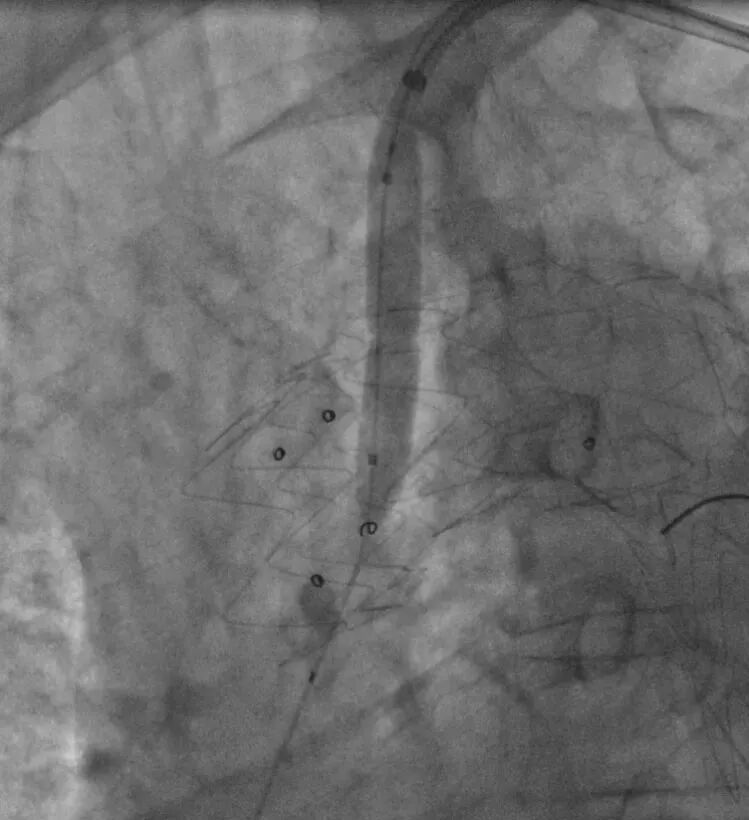

5. 左锁骨下动脉造影示:左锁骨下动脉少量造影剂外漏,根据术前计划,置入12-58mm LifeStream球扩覆膜支架,短肩球囊设计,避免导丝缠绕,顺利通过病变,并扩张释放。

导入LifeStream支架

球扩LifeStream支架

6. 最后造影效果满意,胸主动脉支架位置良好,血流通畅,无明显内漏,弓上三分支血供良好,左锁骨下动脉正向血流、双侧颈动脉和椎动脉显影好,颅内动脉显影好。

LAO术后造影

RAO术后造影